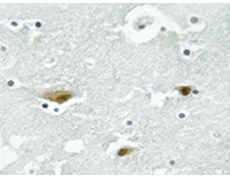

IHC |

IHC positive control: |

Human brain tissue |

IHC Recommend dilution: |

50-100 |